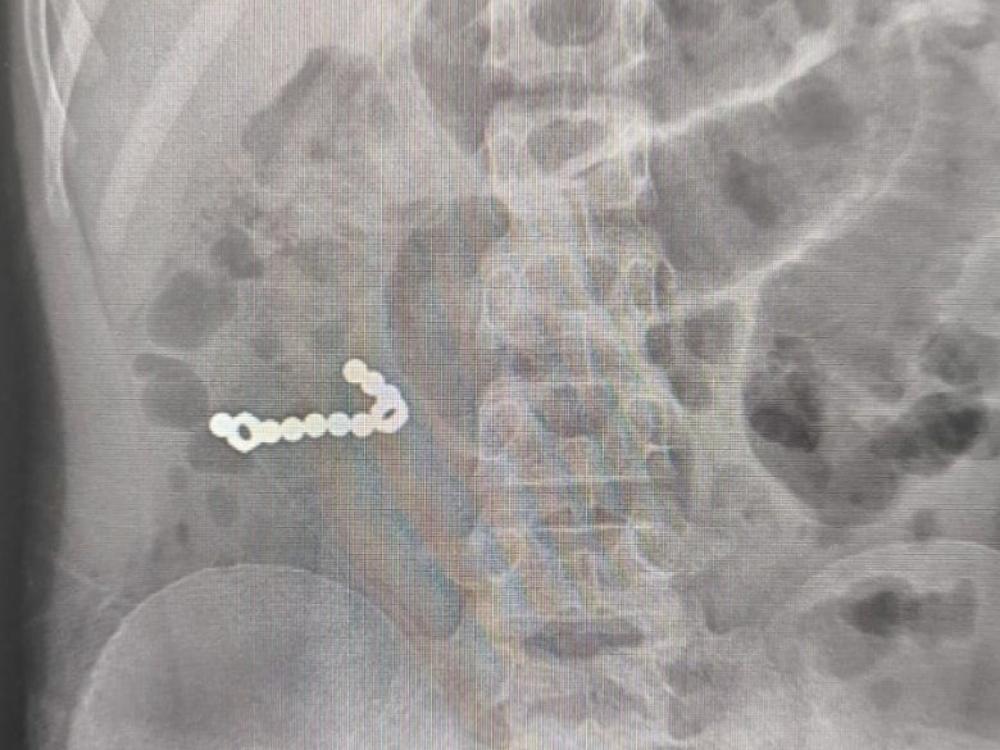

Пациента экстренно доставили в в Коряжемскую ЦГБ, где ему был сделан рентген. На снимке обнаружили множественные инородные тела в ЖКТ. Заведующий хирургическим отделением Дмитрий Кувакин провел вмешательство на органах брюшной полости и извлёк магниты из кишечника.